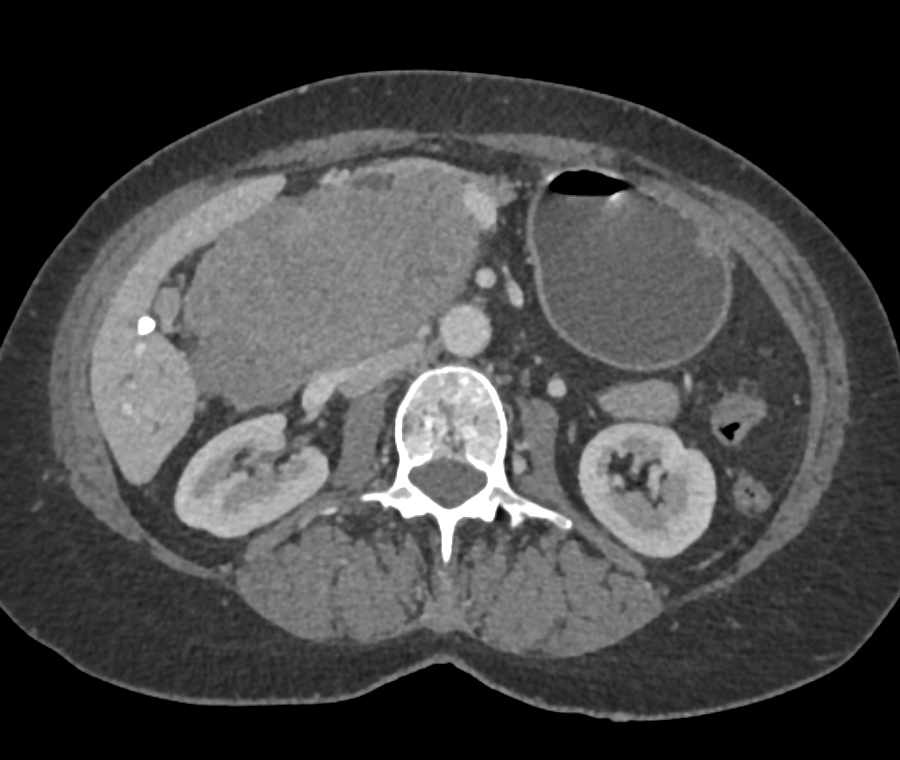

4) The most likely diagnosis in this case is?

adrenal metastases

adrenal lymphoma

adrenal adenoma

adrenal pheochromocytoma